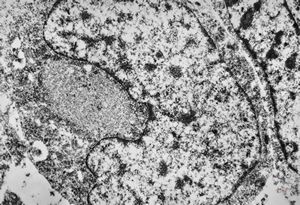

F, 24y. | molluscum contagiosum … virions

F, 24y. | molluscum contagiosum

F, 24y. | molluscum contagiosum